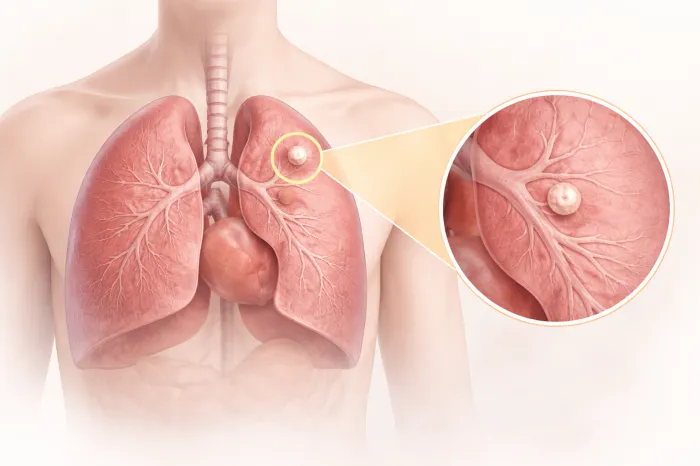

폐결절이란 폐 조직 안에 생긴 작은 덩어리를 의미합니다. 보통 흉부 엑스레이나 CT 검사에서 우연히 발견되는 경우가 많으며, 크기는 대개 3cm 이하입니다. 이보다 큰 경우에는 다른 용어로 구분하기도 합니다. 폐결절은 하나만 보일 수도 있고, 여러 개가 동시에 발견되기도 합니다.

중요한 점은 폐결절이 하나 발견되었다고 해서 모두 심각한 질환을 의미하는 것은 아닙니다. 염증이 남은 흔적일 수도 있고, 과거 감염 이후 생긴 변화일 수도 있습니다. 다만, 정확한 판단을 위해서는 크기, 모양, 위치, 변화 속도 등을 종합적으로 살펴봐야 합니다.